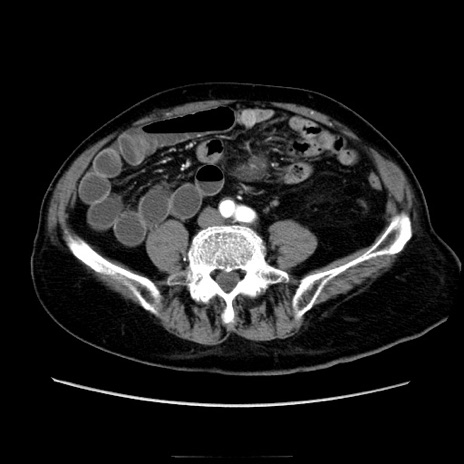

症例21(横断像)

【症例】70歳代男性

【主訴】腹痛

【現病歴】肝硬変・肝細胞癌にてかかりつけの方。約9時間前に食後より腹痛出現。症状が徐々に増悪し、嘔吐出現したため来院。

【既往歴】肝硬変、肝細胞癌(RFA、TACE後)

【身体所見】意識清明、表情苦悶様、BT 36℃、BP 129/78mmHg、P 88bpm、SpO2 97%(RA)、右上腹部から心窩部にかけて圧痛あり、反跳痛なし、筋性防御あり。

【データ】WBC 5800、CRP 0.16